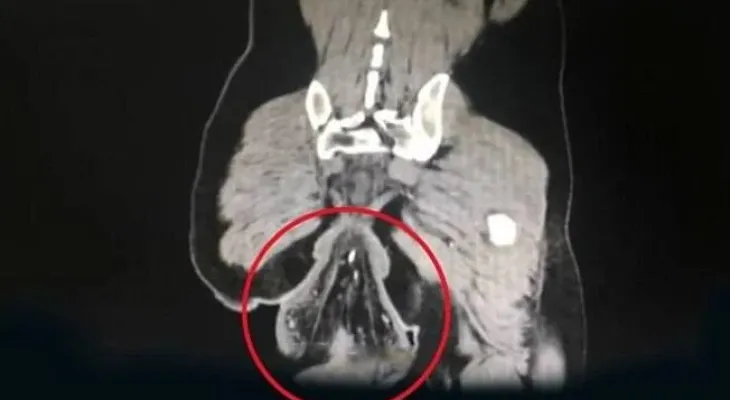

Su disse que o homem foi diagnosticado com prolapso retal, uma condição que vê a última parte dos intestinos perder o apego ao corpo e tornar-se visível do exterior do corpo. A médica disse que a situação do paciente era grave.

“O paciente teve prolapso retal desde os quatro anos de idade, mas a protuberância foi capaz de se retrair no passado”, disse Su, segundo o jornal inglês Daily Mail, que citou “fontes chinenas”. A médica acrescentou: “Ele não teve a doença tratada, então a situação piorou”.